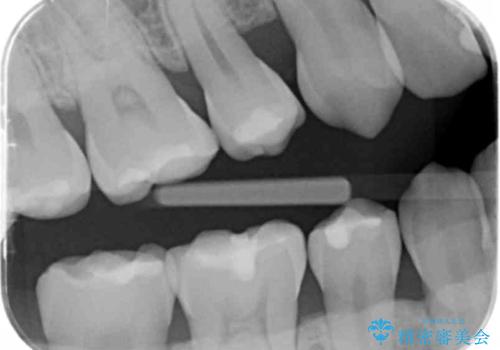

奥歯が欠けた セラミックインレーでの修復後、ナイトガード装着

- 右下の奥歯が欠けたとのことで来院されました。

欠けた部分にはセラミックインレーで修復処置を行い、今後の破折リスクを抑えるためにナイトガードを製作していきます。

- 右下7 セラミックインレー 77,000円/ナイトガード 33,000円費用は治療当時の料金となります